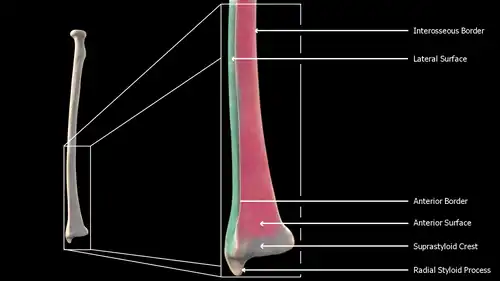

Near the wrist

The distal end of the radius is large and of quadrilateral form.

- Joint surfaces

It is provided with two articular surfaces – one below, for the carpus, and another at the medial side, for the ulna.

- The carpal articular surface is triangular, concave, smooth, and divided by a slight antero-posterior ridge into two parts. Of these, the lateral, triangular, articulates with the scaphoid bone; the medial, quadrilateral, with the lunate bone.

- The articular surface for the ulna is called the ulnar notch (sigmoid cavity) of the radius; it is narrow, concave, smooth, and articulates with the head of the ulna.

These two articular surfaces are separated by a prominent ridge, to which the base of the triangular articular disk is attached; this disk separates the wrist-joint from the distal radioulnar articulation.

- Other surfaces

This end of the bone has three non-articular surfaces – volar, dorsal, and lateral.

- The volar surface, rough and irregular, affords attachment to the volar radiocarpal ligament.

- The dorsal surface is convex, affords attachment to the dorsal radiocarpal ligament, and is marked by three grooves. Enumerated from the lateral side:

- The first groove is broad, but shallow, and subdivided into two by a slight ridge: the lateral of these two, transmits the tendon of the extensor carpi radialis longus muscle; the medial, the tendon of the extensor carpi radialis brevis muscle.

- The second is deep but narrow, and bounded laterally by a sharply defined ridge; it is directed obliquely from above downward and lateralward, and transmits the tendon of the extensor pollicis longus muscle.

- The third is broad, for the passage of the tendons of the extensor indicis proprius and extensor digitorum communis.

- The lateral surface is prolonged obliquely downward into a strong, conical projection, the styloid process, which gives attachment by its base to the tendon of the brachioradialis, and by its apex to the radial collateral ligament of wrist joint. The lateral surface of this process is marked by a flat groove, for the tendons of the abductor pollicis longus muscle and extensor pollicis brevis muscle.

Body

The body of the radius (or shaft of radius) is prismoid in form, narrower above than below, and slightly curved, so as to be convex lateralward. It presents three borders and three surfaces.

- Borders

The volar border (margo volaris; anterior border; palmar;) extends from the lower part of the tuberosity above to the anterior part of the base of the styloid process below, and separates the volar from the lateral surface. Its upper third is prominent, and from its oblique direction has received the name of the oblique line of the radius; it gives origin to the flexor digitorum superficialis muscle (also flexor digitorum sublimis) and flexor pollicis longus muscle; the surface above the line gives insertion to part of the supinator muscle. The middle third of the volar border is indistinct and rounded. The lower fourth is prominent, and gives insertion to the pronator quadratus muscle, and attachment to the dorsal carpal ligament; it ends in a small tubercle, into which the tendon of the brachioradialis muscle is inserted.

The dorsal border (margo dorsalis; posterior border) begins above at the back of the neck, and ends below at the posterior part of the base of the styloid process; it separates the posterior from the lateral surface. is indistinct above and below, but well-marked in the middle third of the bone.

The interosseous border (internal border; crista interossea; interosseous crest;) begins above, at the back part of the tuberosity, and its upper part is rounded and indistinct; it becomes sharp and prominent as it descends, and at its lower part divides into two ridges which are continued to the anterior and posterior margins of the ulnar notch. To the posterior of the two ridges the lower part of the interosseous membrane is attached, while the triangular surface between the ridges gives insertion to part of the pronator quadratus muscle. This crest separates the volar from the dorsal surface, and gives attachment to the interosseous membrane. The connection between the two bones is actually a joint referred to as a syndesmosis joint.

The lateral surface (facies lateralis; external surface) is convex throughout its entire extent and is known as the convexity of the radius, curving outwards to be convex at the side. Its upper third gives insertion to the supinator muscle. About its center is a rough ridge, for the insertion of the pronator teres muscle.[3] Its lower part is narrow, and covered by the tendons of the abductor pollicis longus muscle and extensor pollicis brevis muscle.

Lateral view of right distal radius

Lateral view of right distal radius -